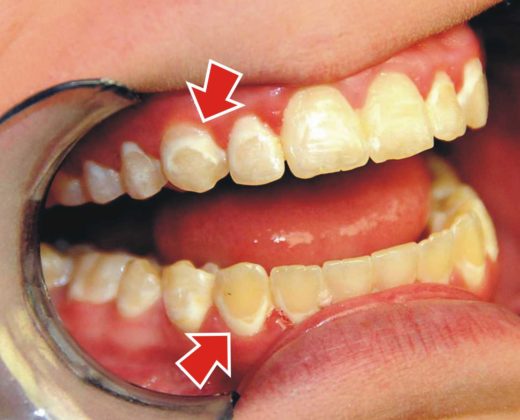

La Parodontologia è un ramo dell’Odontoiatria, che si occupa dello studio delle malattie che riguardano la bocca ed in modo particolare dei denti. Il parodonto è costituito da : gengiva; osso alveolare; cemento radicolare...